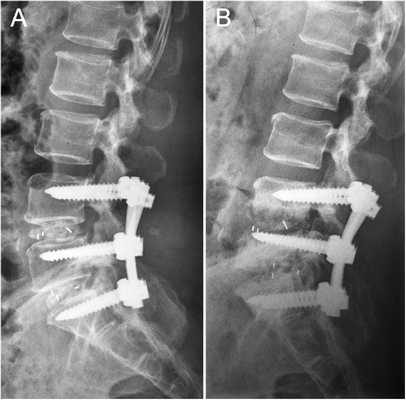

Стабилизационная система на рентгене.

Кейджы межпозвоночных дисков поясничного отдела.

Стабилизация поясничного отдела.